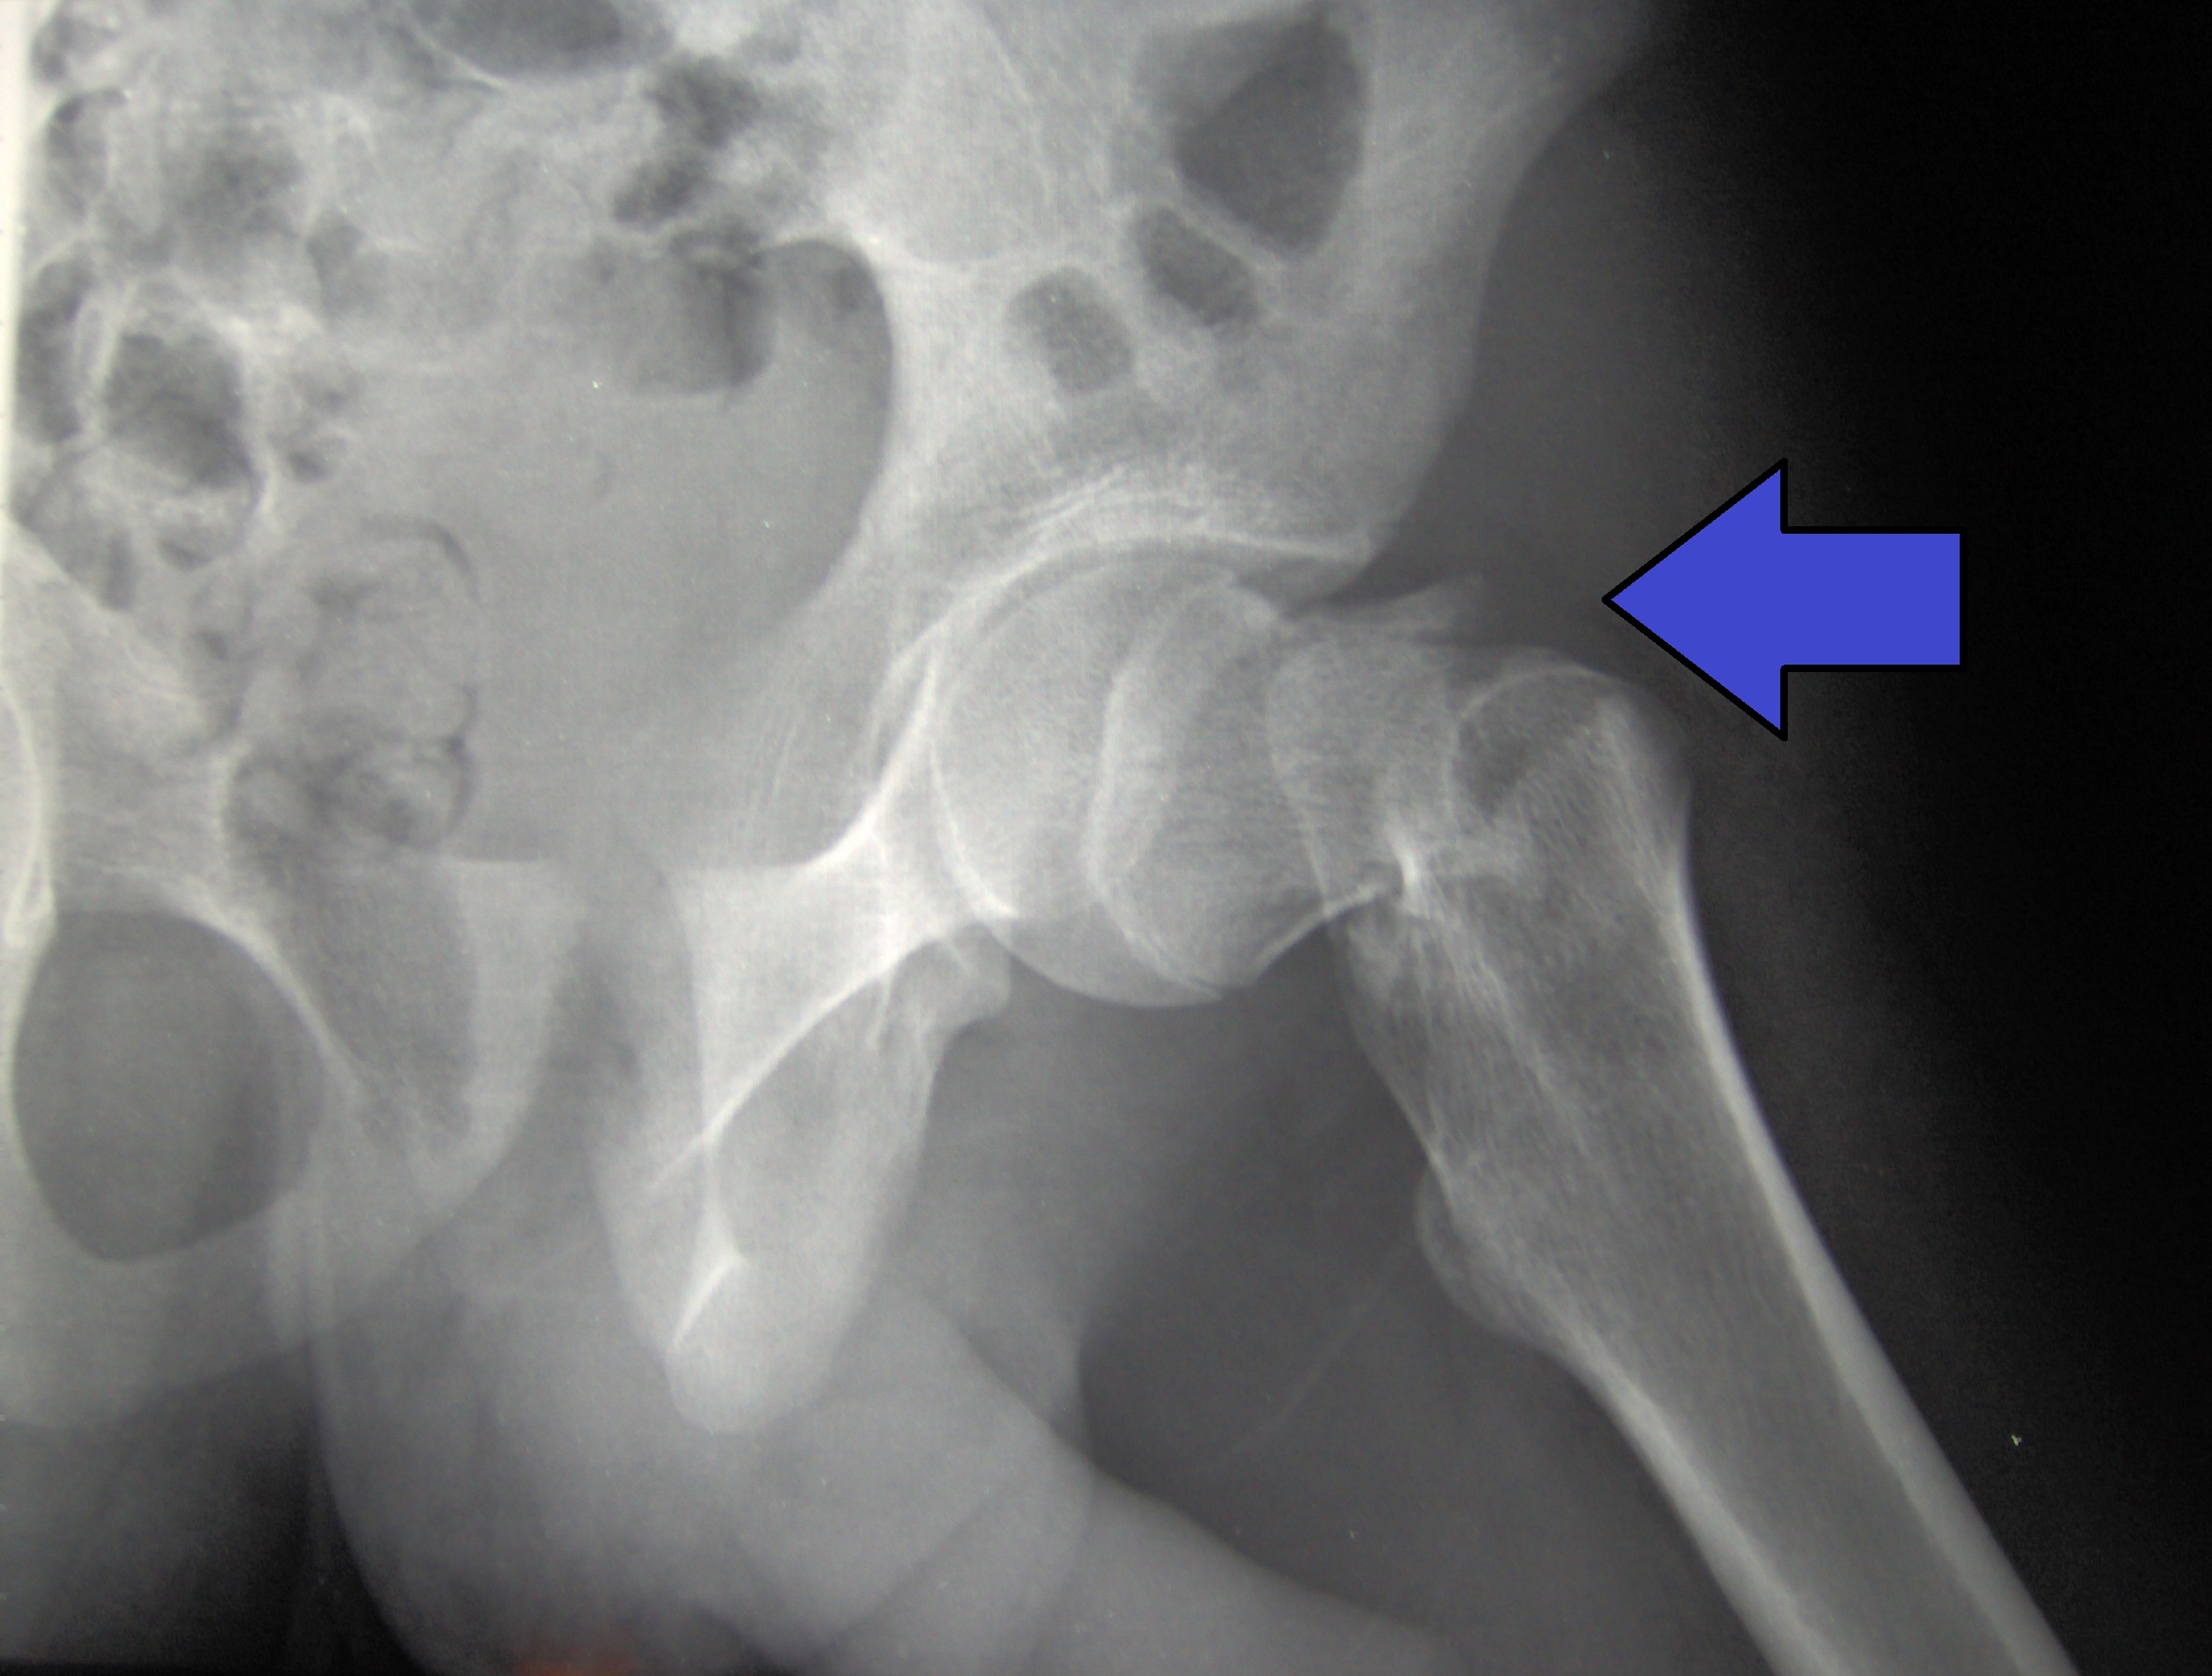

Una segunda evaluación de la DMO a los 3 años de la medición basal no se asoció con una mejor discriminación entre las mujeres que experimentaron y no experimentaron una fractura de cadera posterior o una fractura osteoporótica mayor, y no debe realizarse de forma rutinaria. JAMA Internal Medicine, julio de 2020.